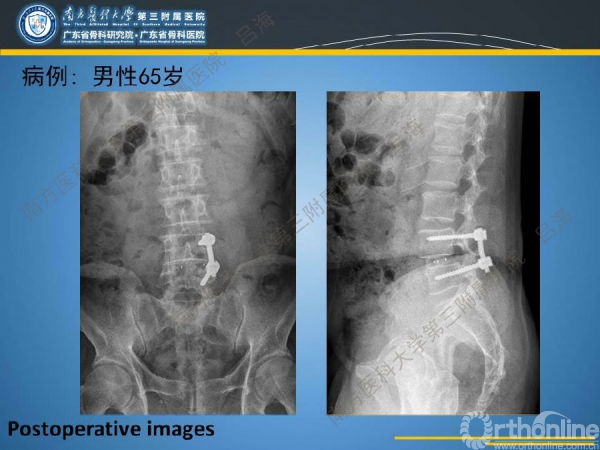

随着社会老龄化进程加快,胸腰椎退行性病变的治疗已经成为脊柱学术界的一个热点话题。MIS-TLIF手术可以治疗多种不同的胸腰椎退行性疾病,南方医科大学第三附属医院吕海教授结合病例为我们一一展示了该术式在治疗不同胸腰椎疾病时的具体手术过程。